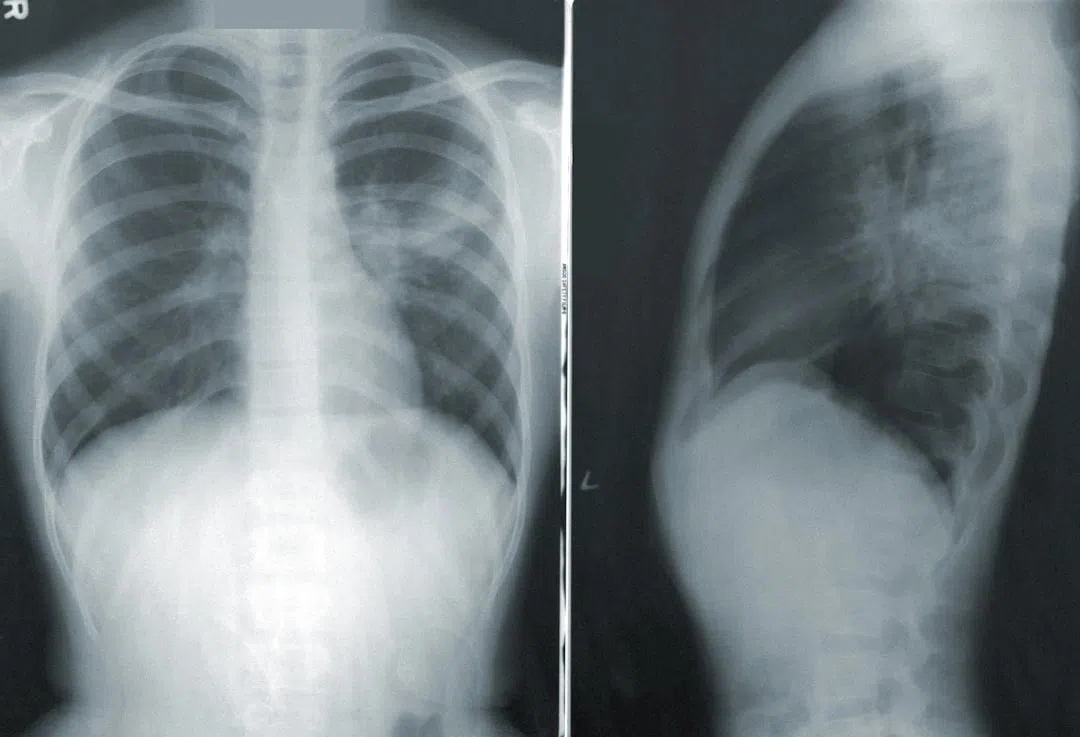

어떻게 진단할까요?

COPD는 폐기능 검사로 진단합니다. 이는 환자의 나이, 성별, 몸무게 등을 기준으로 정상적인 폐 기능과 비교하여 현재 폐 기능이 얼마나 손상되었는지 확인하는 검사입니다.